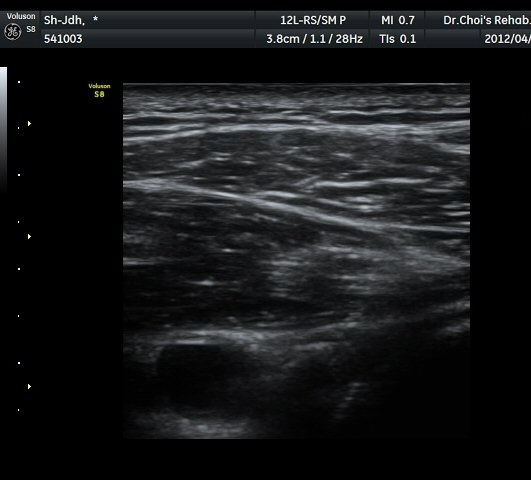

À̵ιڱ٠Ⱦ´Ü¸é°Ë»ç¿¡¼­ À̵ιڱٰÇÀÇ ºñÈĸ¦ º¸ÀÓ(»çÁø 1, 2).

À̵ιڱٰú ÀÌ¿ôÇÑ °ß°©ÇÏ±Ù°Ç »óºÎ¿¡¼­ ±¹¼ÒÀûÀÎ ¿¬°á¼º ¼Ò½ÇÀÌ °üÂûµÊ(»çÁø 3).